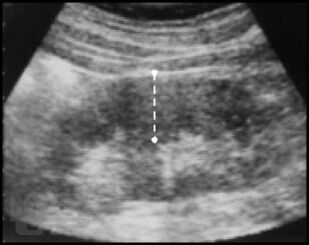

Настоящая монография предназначена для врачей – лучевых диагностов, урологов, хирургов, терапевтов, семейных врачей, а также студентов медицинских вузов, и посвящена применению лучевых методов исследования в диагностике различных форм острого гнойного пиелонефрита.

В монографии детально показана разнообразная лучевая семиотика при апостематозном пиелонефрите, карбункуле и абсцессе почки, а также представлены различные современные методы лечения с динамикой воспалительных изменений в паренхиме почки.